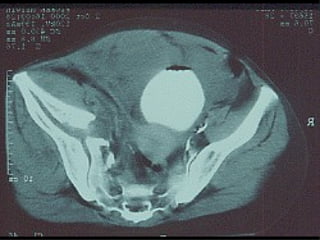

Tc pre op